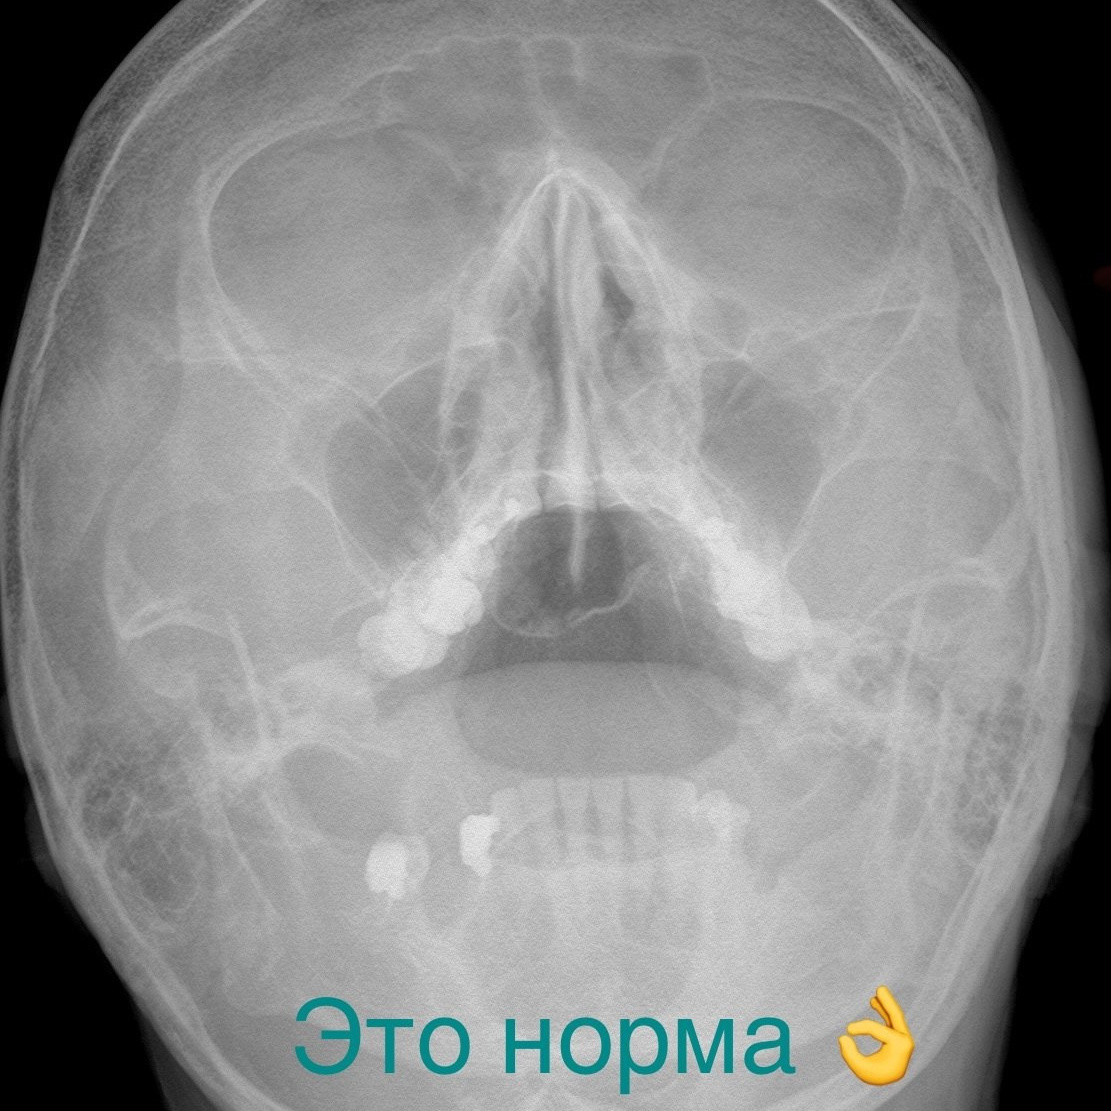

Этот вопрос ставит в тупик не только пациентов, но и бывалых терапевтов, гастроэнтерологов, лор-врачей и многих...